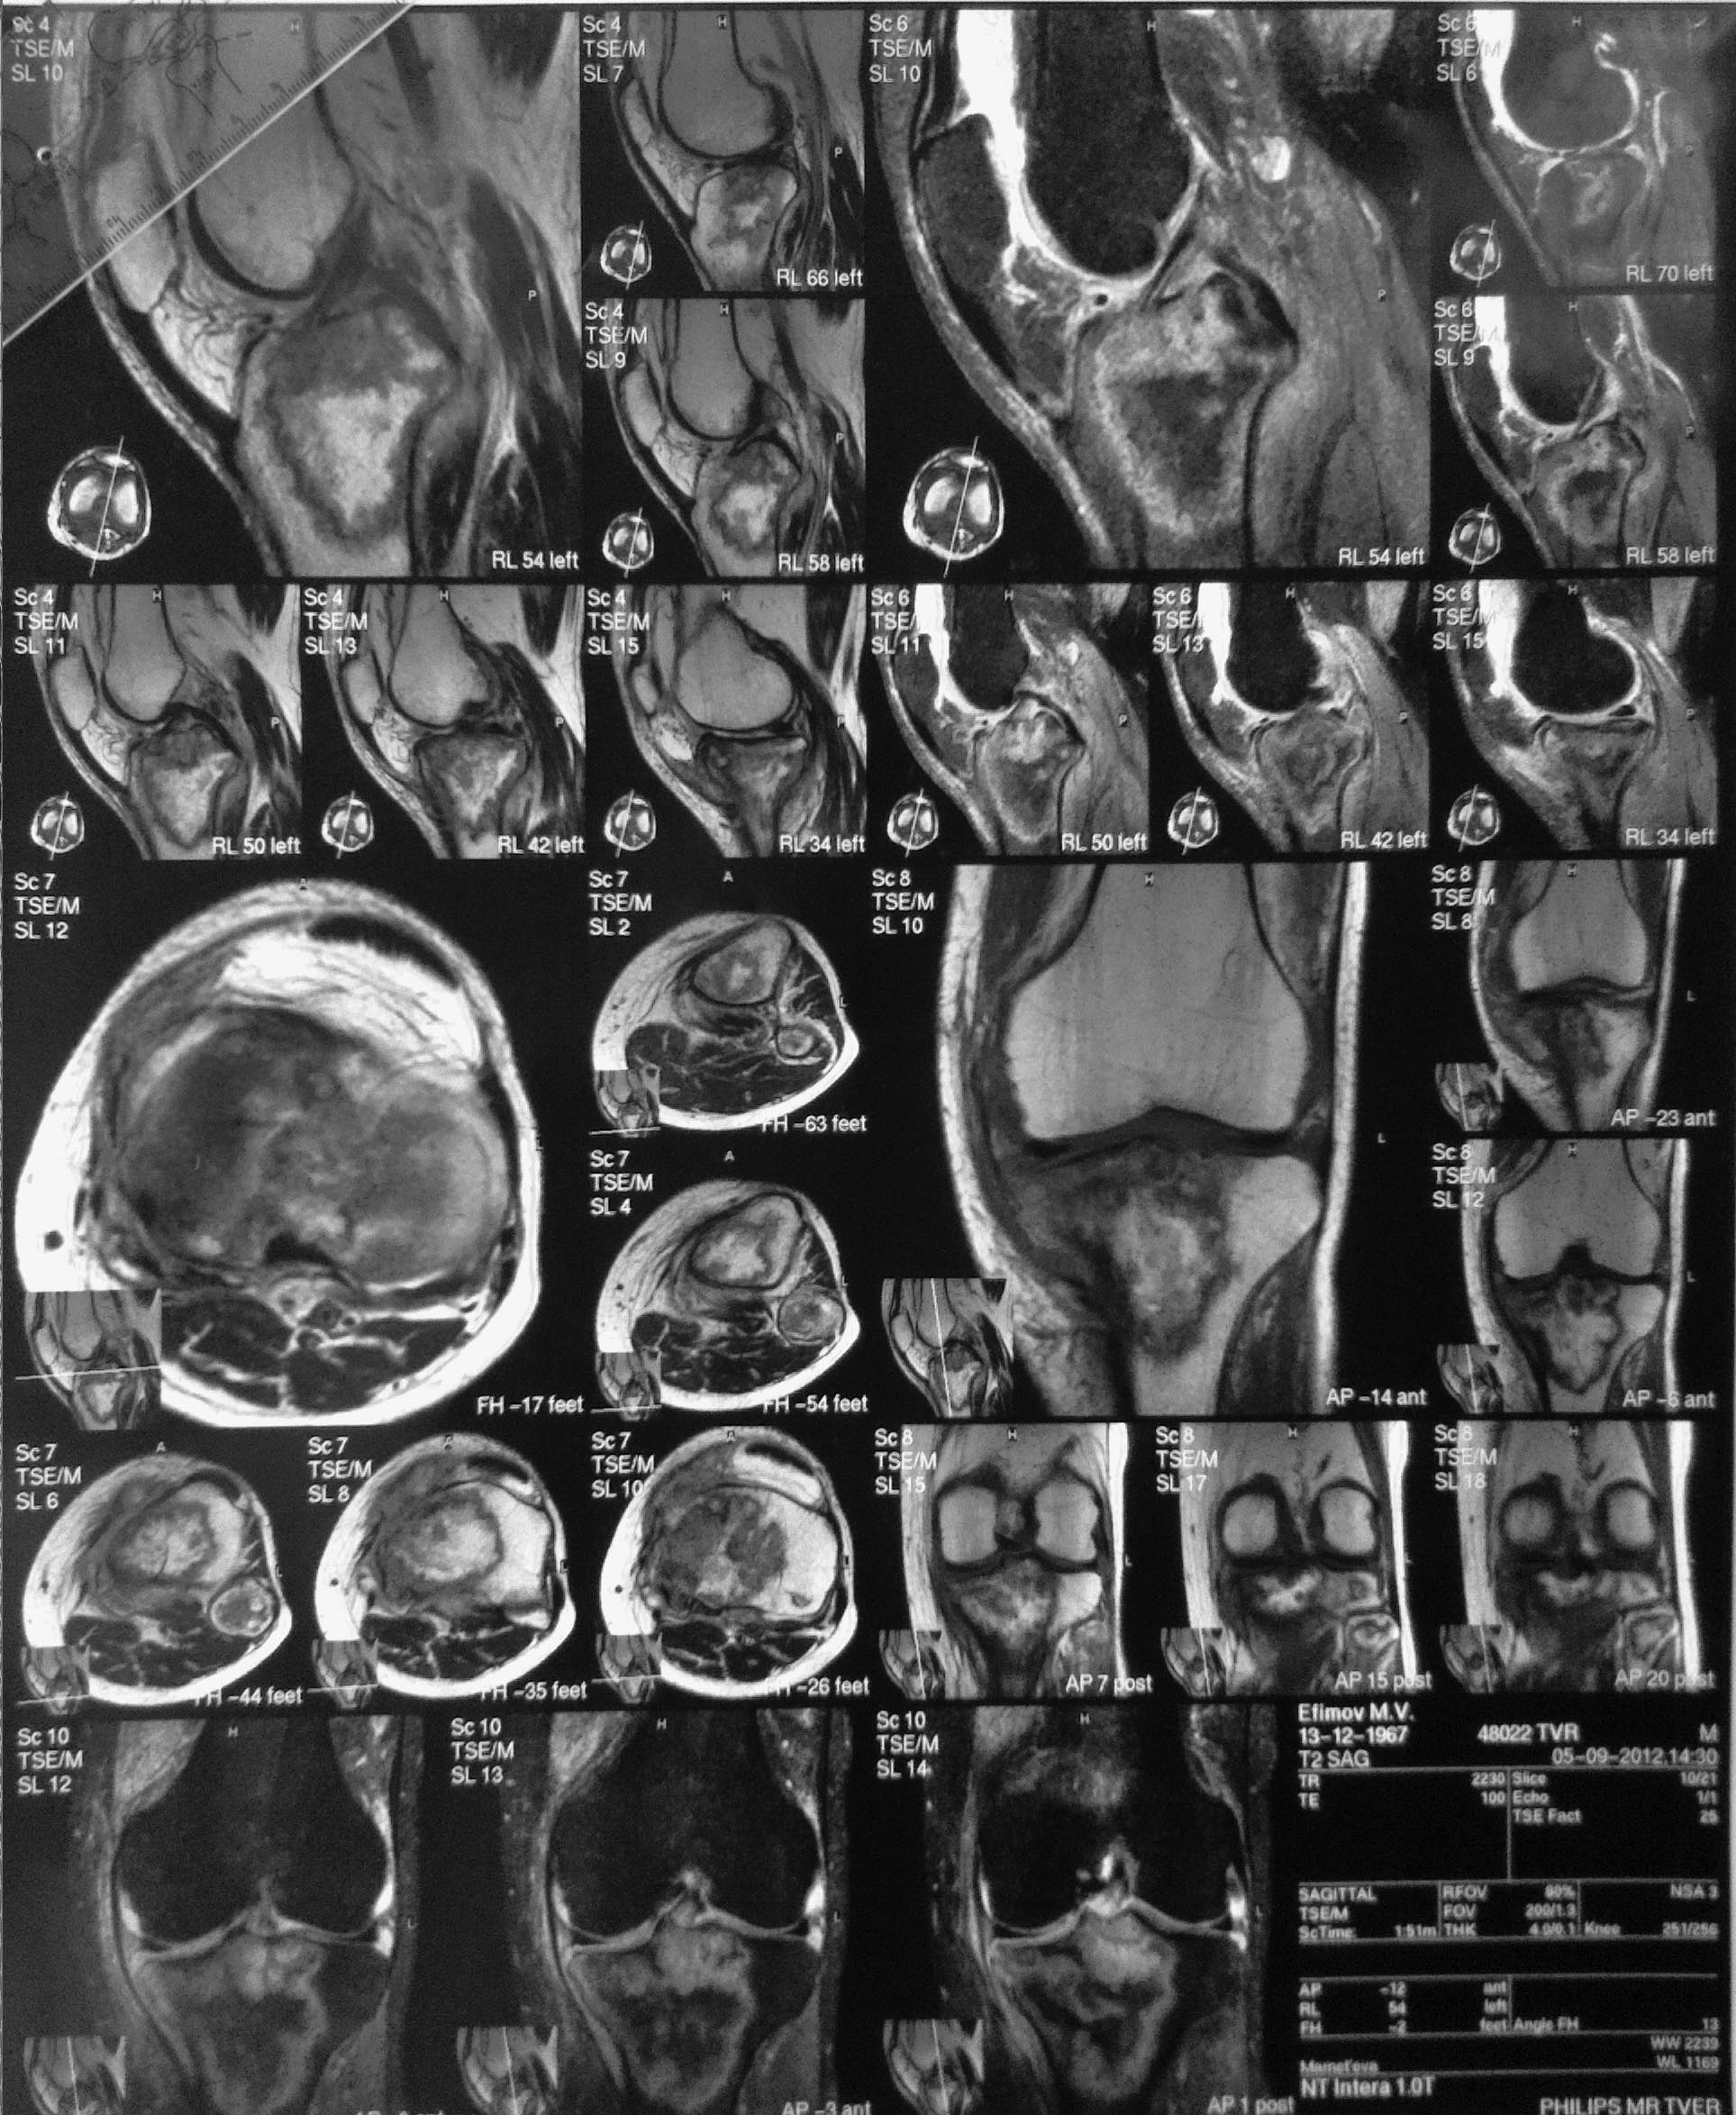

Мужчина 46 лет, электрик РЖД. Болен год. Боли в левом коленном суставе.

Ходит с тростью с апр 2012, конечность опорная, функция сустава сохранена, внешне сустав интактен, отека, гиперемии, жидкости в суставе - нет. Нормального телосложения и питания, активный. Амплитуда движений почти полная, болезненность при макс. сгибании.

Сцинтиграфия с Технецием - патологическое накопление 200%, других участков гиперфиксации изотопа нет.

МРТ - сент 2012